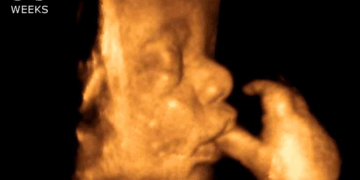

One of the primary marks of a nation is how it cares for its most vulnerable. Few are more vulnerable and helpless than the preborn. Every child in a mother’s womb is humanity’s tomorrow. That is, after all, how each of us started. Those tiny…